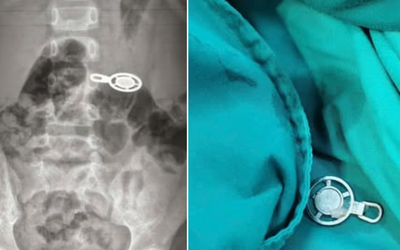

Những "lá chắn" thầm lặng phía sau ánh đèn phòng mổ

Sức khỏe Thứ 6, 27/02/2026 | 19:40

Nhân Ngày Thầy thuốc Việt Nam 27/2, nhìn lại phía sau những ca mổ thành công, có thể thấy rõ hình bóng những con người làm việc không cần hào quang, họ giữ “vùng sạch”, giữ “dòng thuốc” và giữ niềm tin cho người bệnh.